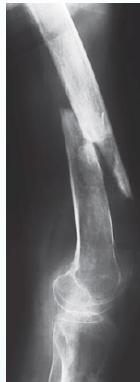

- Bone deformity. (vertebral bodies are biconcave, the femora may be bowed)

Vertebral bodies are biconcave